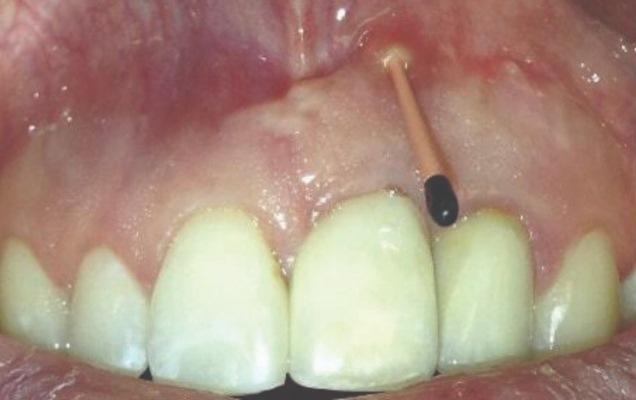

Заживление в обоих случаях протекало без осложнений, без неблагоприятных исходов. В случае 1 наблюдалось хорошее заживление с разрешением свищевого хода через 3 месяца после операции. Рентгеновские снимки на контрольных осмотрах через 6 и 9 месяцев продемонстрировали увеличение рентгеноконтрастности кости с полным рентгенологическим костным наполнением к 12 месяцам (Фото 13 и Фото 14).

Фото 13 и Фото 14. Случай 1: Вестибулярный вид (Фото 13) и рентгеновский снимок (Фото 14) на контрольном осмотре через 12 месяцев, подтверждающие разрешение РПИ.